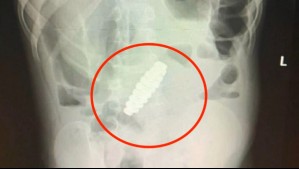

Mundo Llevaron a su hijo al doctor por una posible apendicitis, pero tenía un extraño objeto en sus intestinos